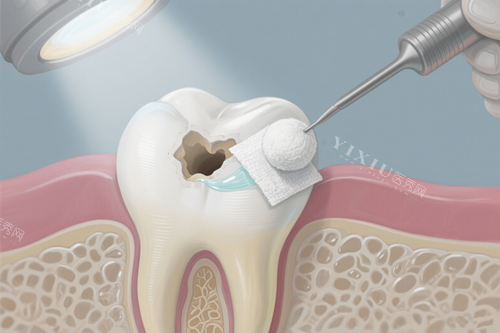

牙医会检查牙洞深度,可能建议进行填充治疗,就是把蛀坏部分清除后,用安心材料补上,改善牙齿功能。

对于更严峻的情况,比如感染到牙髓,可能需要根管治疗,但现代技术已经很成熟,过程相对舒适。